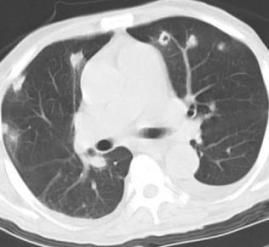

The patient was listless, diaphoretic, and appeared to be using accessory muscles of respiration. Temperature was 39°C (102.2°F); pulse, 120 beats/min; and blood pressure, 106/50 mm Hg. Examination of the chest revealed decreased air entry at bases. Heart sounds were normal without murmurs. Findings from the abdominal and neurologic examinations were normal, and there was no evidence of leg swelling. Hemoglobin concentration was 14.4 g/L, and white blood cell count was 19.3 x 109/L (polymorphonuclear leukocytes 77%, band forms 16%, eosinophils 4%, and monocytes 3%). Figures 1 and 2 show CT scans of the chest. Results of a lumbar puncture and a CT scan of the brain were unremarkable. Transesophageal echocardiography (TEE) found no cardiac vegetations. A culture taken from the catheter tip was positive for methicillin-sensitive Staphylococcusaureus.

Figure 1.

As seen in the Figures, CT scan of the chest found multiple subpleural peripheral nodules. Some lesions revealed cavitation, a finding consistent with septic pulmonary emboli (PE), given the confounding clinical findings of this patient.

The major findings on chest CT scan are multiple pulmonary peripheral nodules of varying size with evidence of cavitation.5 Mediastinal lymphadenopathy and/or peripheral wedge-shaped densities along the pleura and hilar are also possible.6 TEE is essential to rule out right-sided endocarditis as a source.